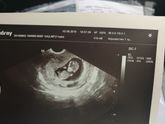

2 августа 2019 16:32 Позже писала пост, что ходила на приём к гине, и она доплером не нашла сердечко ещё. Это был понедельник этот, сегодня ходила опять, и опять она пробовала, и нашлось наше сердечко? 158ударов/в минуту, ура ?❤️